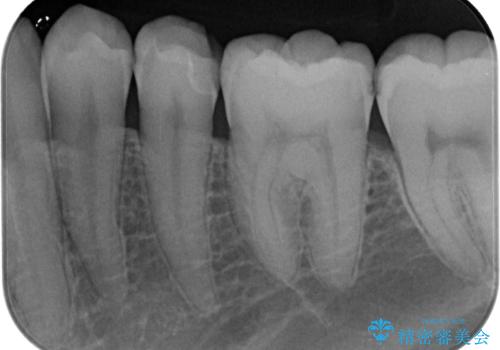

- 左下の奥歯のところがフロスが引っかかったり、ちぎれたりするとのことで来院された患者様です。検査の結果、神経は正常な反応を示し、フロスは引っかかる状態でしたので、虫歯治療も併せて行うためにオールセラミッククラウンによる補綴治療を行っていくことにしました。

拡大鏡視野下でプラスチックの詰め物、虫歯を除去しオールセラミッククラウンに適した形に整えました。